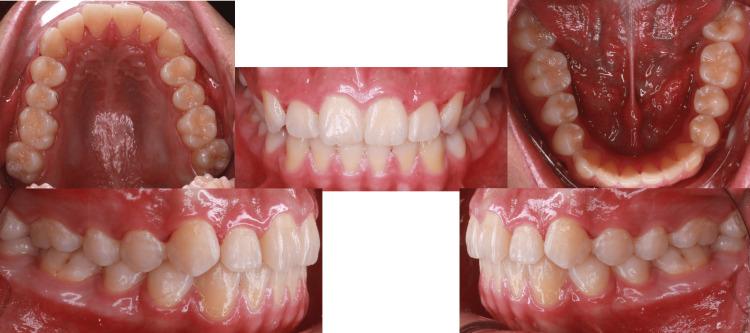

Clear aligner therapy has significantly improved orthodontic treatment by offering patients a more aesthetically pleasing option compared to traditional braces. This literature review and case report specifically focus on the effectiveness of directly printed clear aligners in treating Class II malocclusions and crowding. Class II malocclusions are characterized by excessive overjet, which often results from skeletal or dental discrepancies between the upper and lower jaws. Crowding refers to the lack of space for teeth within the dental arch, leading to misalignment and potential functional issues. The review and case report highlight the increasing importance of directly printed clear aligners in modern orthodontics and provide clinicians with a valuable tool to effectively address complex malocclusions and crowding while also meeting patient needs for discretion and comfort. Further research is necessary to validate the long-term stability and outcomes of directly printed clear aligner therapy in various orthodontic cases. A detailed case report demonstrates the successful treatment of a patient with Class II malocclusion and mild crowding using directly printed clear aligners. Treatment outcomes include improvements in dental alignment, occlusion, and facial aesthetics, showcasing the effectiveness of this innovative approach.

与传统牙套相比,隐形矫治器疗法为患者提供了更美观的选择,显著改善了正畸治疗。这篇文献综述和病例报告特别关注直接打印的隐形矫治器在治疗II类错颌畸形和牙列拥挤方面的有效性。II类错颌畸形的特征是覆盖过大,这通常是由于上下颌之间的骨骼或牙齿差异所致。牙列拥挤是指牙弓内牙齿缺乏空间,导致牙齿排列不齐和潜在的功能问题。该综述和病例报告强调了直接打印的隐形矫治器在现代正畸学中日益重要的地位,并为临床医生提供了一种有价值的工具,既能有效解决复杂的错颌畸形和牙列拥挤问题,又能满足患者对美观和舒适的需求。有必要进行进一步的研究,以验证直接打印的隐形矫治器疗法在各种正畸病例中的长期稳定性和治疗效果。一份详细的病例报告展示了使用直接打印的隐形矫治器成功治疗一名II类错颌畸形和轻度牙列拥挤患者的过程。治疗结果包括牙齿排列、咬合和面部美观的改善,展示了这种创新方法的有效性。